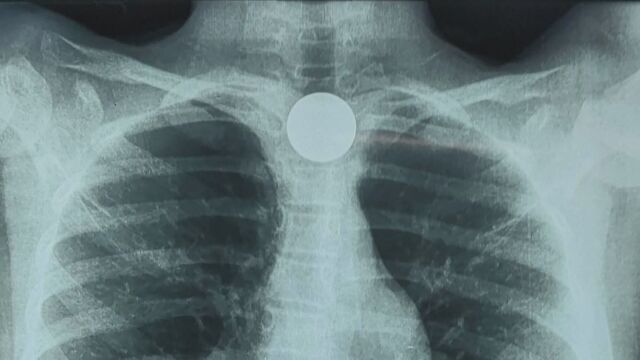

9-годишно момиче погълна голяма монета, която се заклещи в хранопровода ѝ. Това е четвърти подобен случай с деца през тази година във Фернандо де ла Мора, Парагвай.

Там лекарите извършили езофагоскопия, за да извадят монетата безопасно.

„Вчера пристъпихме към изваждане на монетата, която се беше заклещила в хранопровода. Тя не причиняваше дискомфорт при преглъщане, само малко слюноотделяне“, обясни д-р Мориниго.